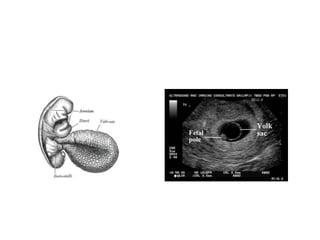

Pelvic ultrasound

• Most useful test in diagnostic evaluation of

women with suspected spontaneous abortion

• Foetal cardiac activity: most important (5.5-

6wks)

• Foetal heart rate

• Size & contour of G.sac

• Presence of yolk sac

• Best evaluated ,transvaginal approach(TVS)

• #16 The gestational sac (GS) is the first sign of early pregnancy on ultrasound and can be seen with endovaginal ultrasound at approximately 3-5 weeks gestation when the mean sac diameter (MSD) would approximately measure 2-3 mm in diameter.

• #17 The yolk sac is a membranous sac attached to an embryo, formed by cells of the hypoblast adjacent to the embryonic disk. The yolk sac is important in early embryonic blood supply, and much of it is incorporated into the primordial gut during the fourth week of development.